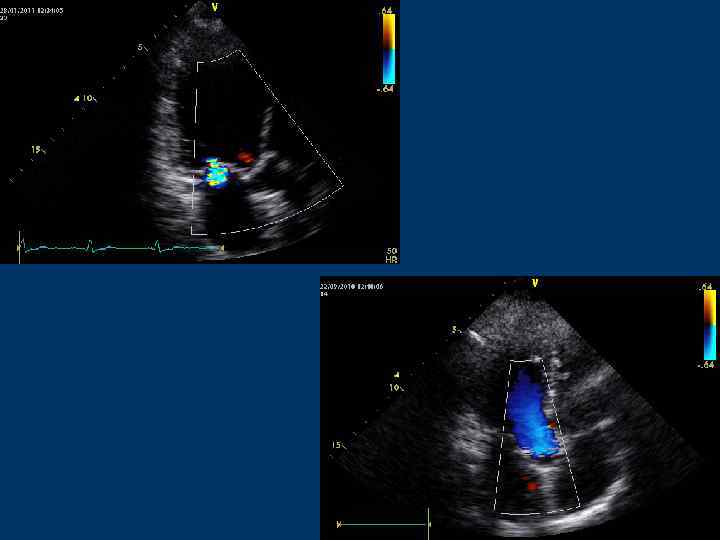

Цветное допплеровское сканирование (Color Doppler)

Color Doppler